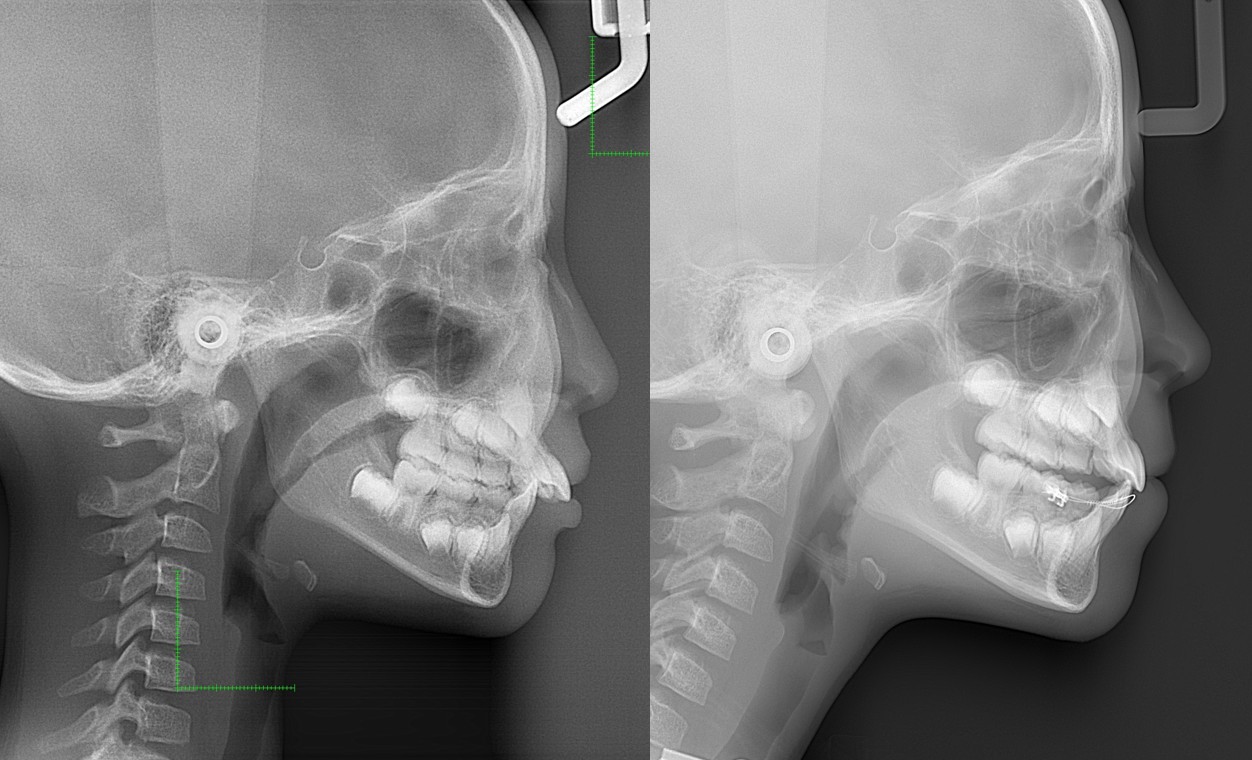

顎変形症:下の歯(顎)が出ている。また、下顎側方偏位:(あごまがり)である

下顎側方偏位:あごまがり

・主訴:下あごが出ている。顎が曲がっている。

・診断:骨格性下顎前突

・年齢:20歳

・使用した主な装置:マルチブラケット装置

・抜歯部位:第一小臼歯を4本抜去

・治療期間:30か月

・通院回数:30回

・費用の目安:保険適応。保険矯正代金は、20万円くらい。症状・期間によってかわります。その他大学病院で外科矯正手術代金がかかります。